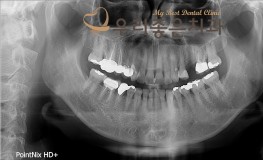

우리좋은치과 임플란트 및 보철치료 (권** 2018.02.24~2018.09.08)

No.203

임플란트

2018-09-15

1293